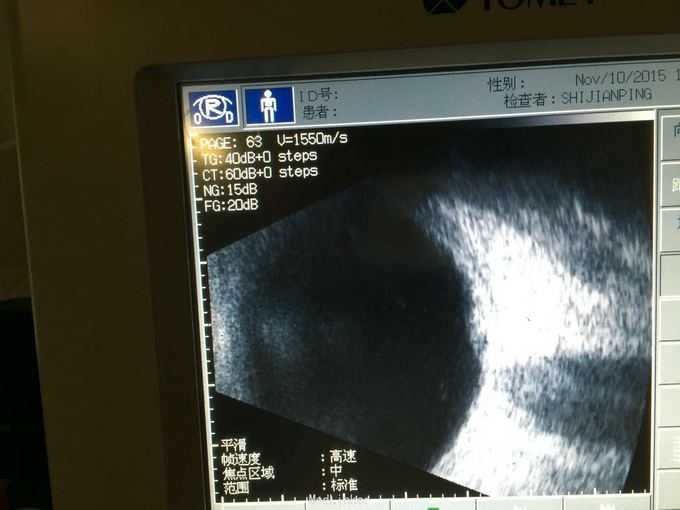

眼底出血(がんていしゅっけつ)は網膜表面の血管の破綻や閉塞することで起こる網膜の出血である。 出血の量自体は微小で貧血などの原因となるものではないが、重度の視力障害を来すこともある。

出血量、出血部位、出血位置、出血後の血行動態等により視力予後が変わる。

等に分類される。出血部位の色調・辺縁の性状にて分類可能である。

出血の位置により

- 黄斑部出血

- 黄斑下出血